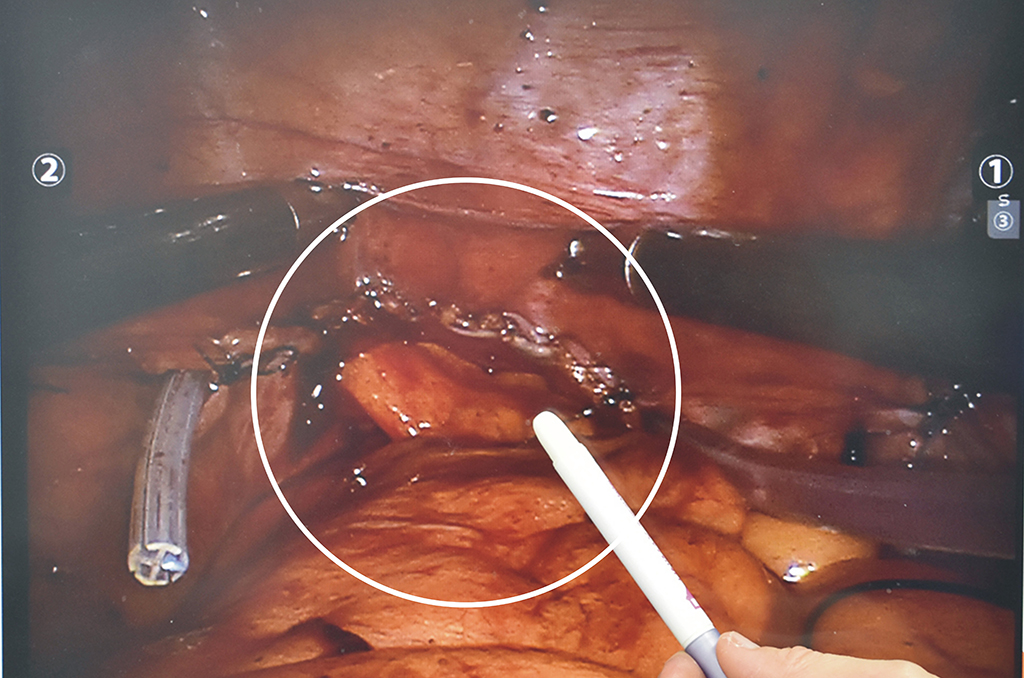

王百孚醫師執行「雷氏空間保留法」之攝護腺根除手術,病患於術後排尿順暢,而且沒有復發現象。

王百孚醫師表示,「雷氏空間保留法」是從膀胱後面進去執行手術,切除攝護腺之後,膀胱與尿道吻合。